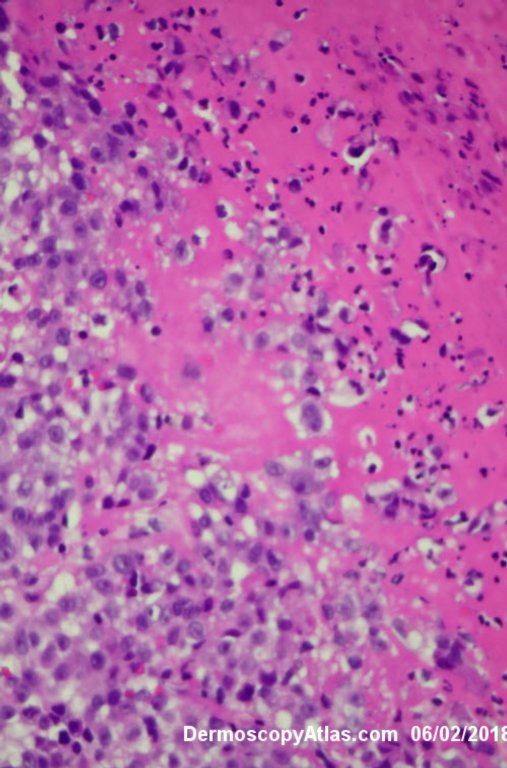

Image Number #3421 (Melanoma invasive)

Site: Leg

Diagnosis: Melanoma invasive

Description: Multiple colours in this pigmented lesion on the lower leg. New pink area

Lady in her early 80s who presented with this lesion on her ankle. The pigmented area had been there for some time but the pink area was bleeding and new. Shave of surrounding area and a punch biopsy of the new pink area showed mainly surrounding in situ melanoma with invasive melanoma in the pink area 1.8 mm thick. Having a 2cms margin excision of the whole area and a graft.